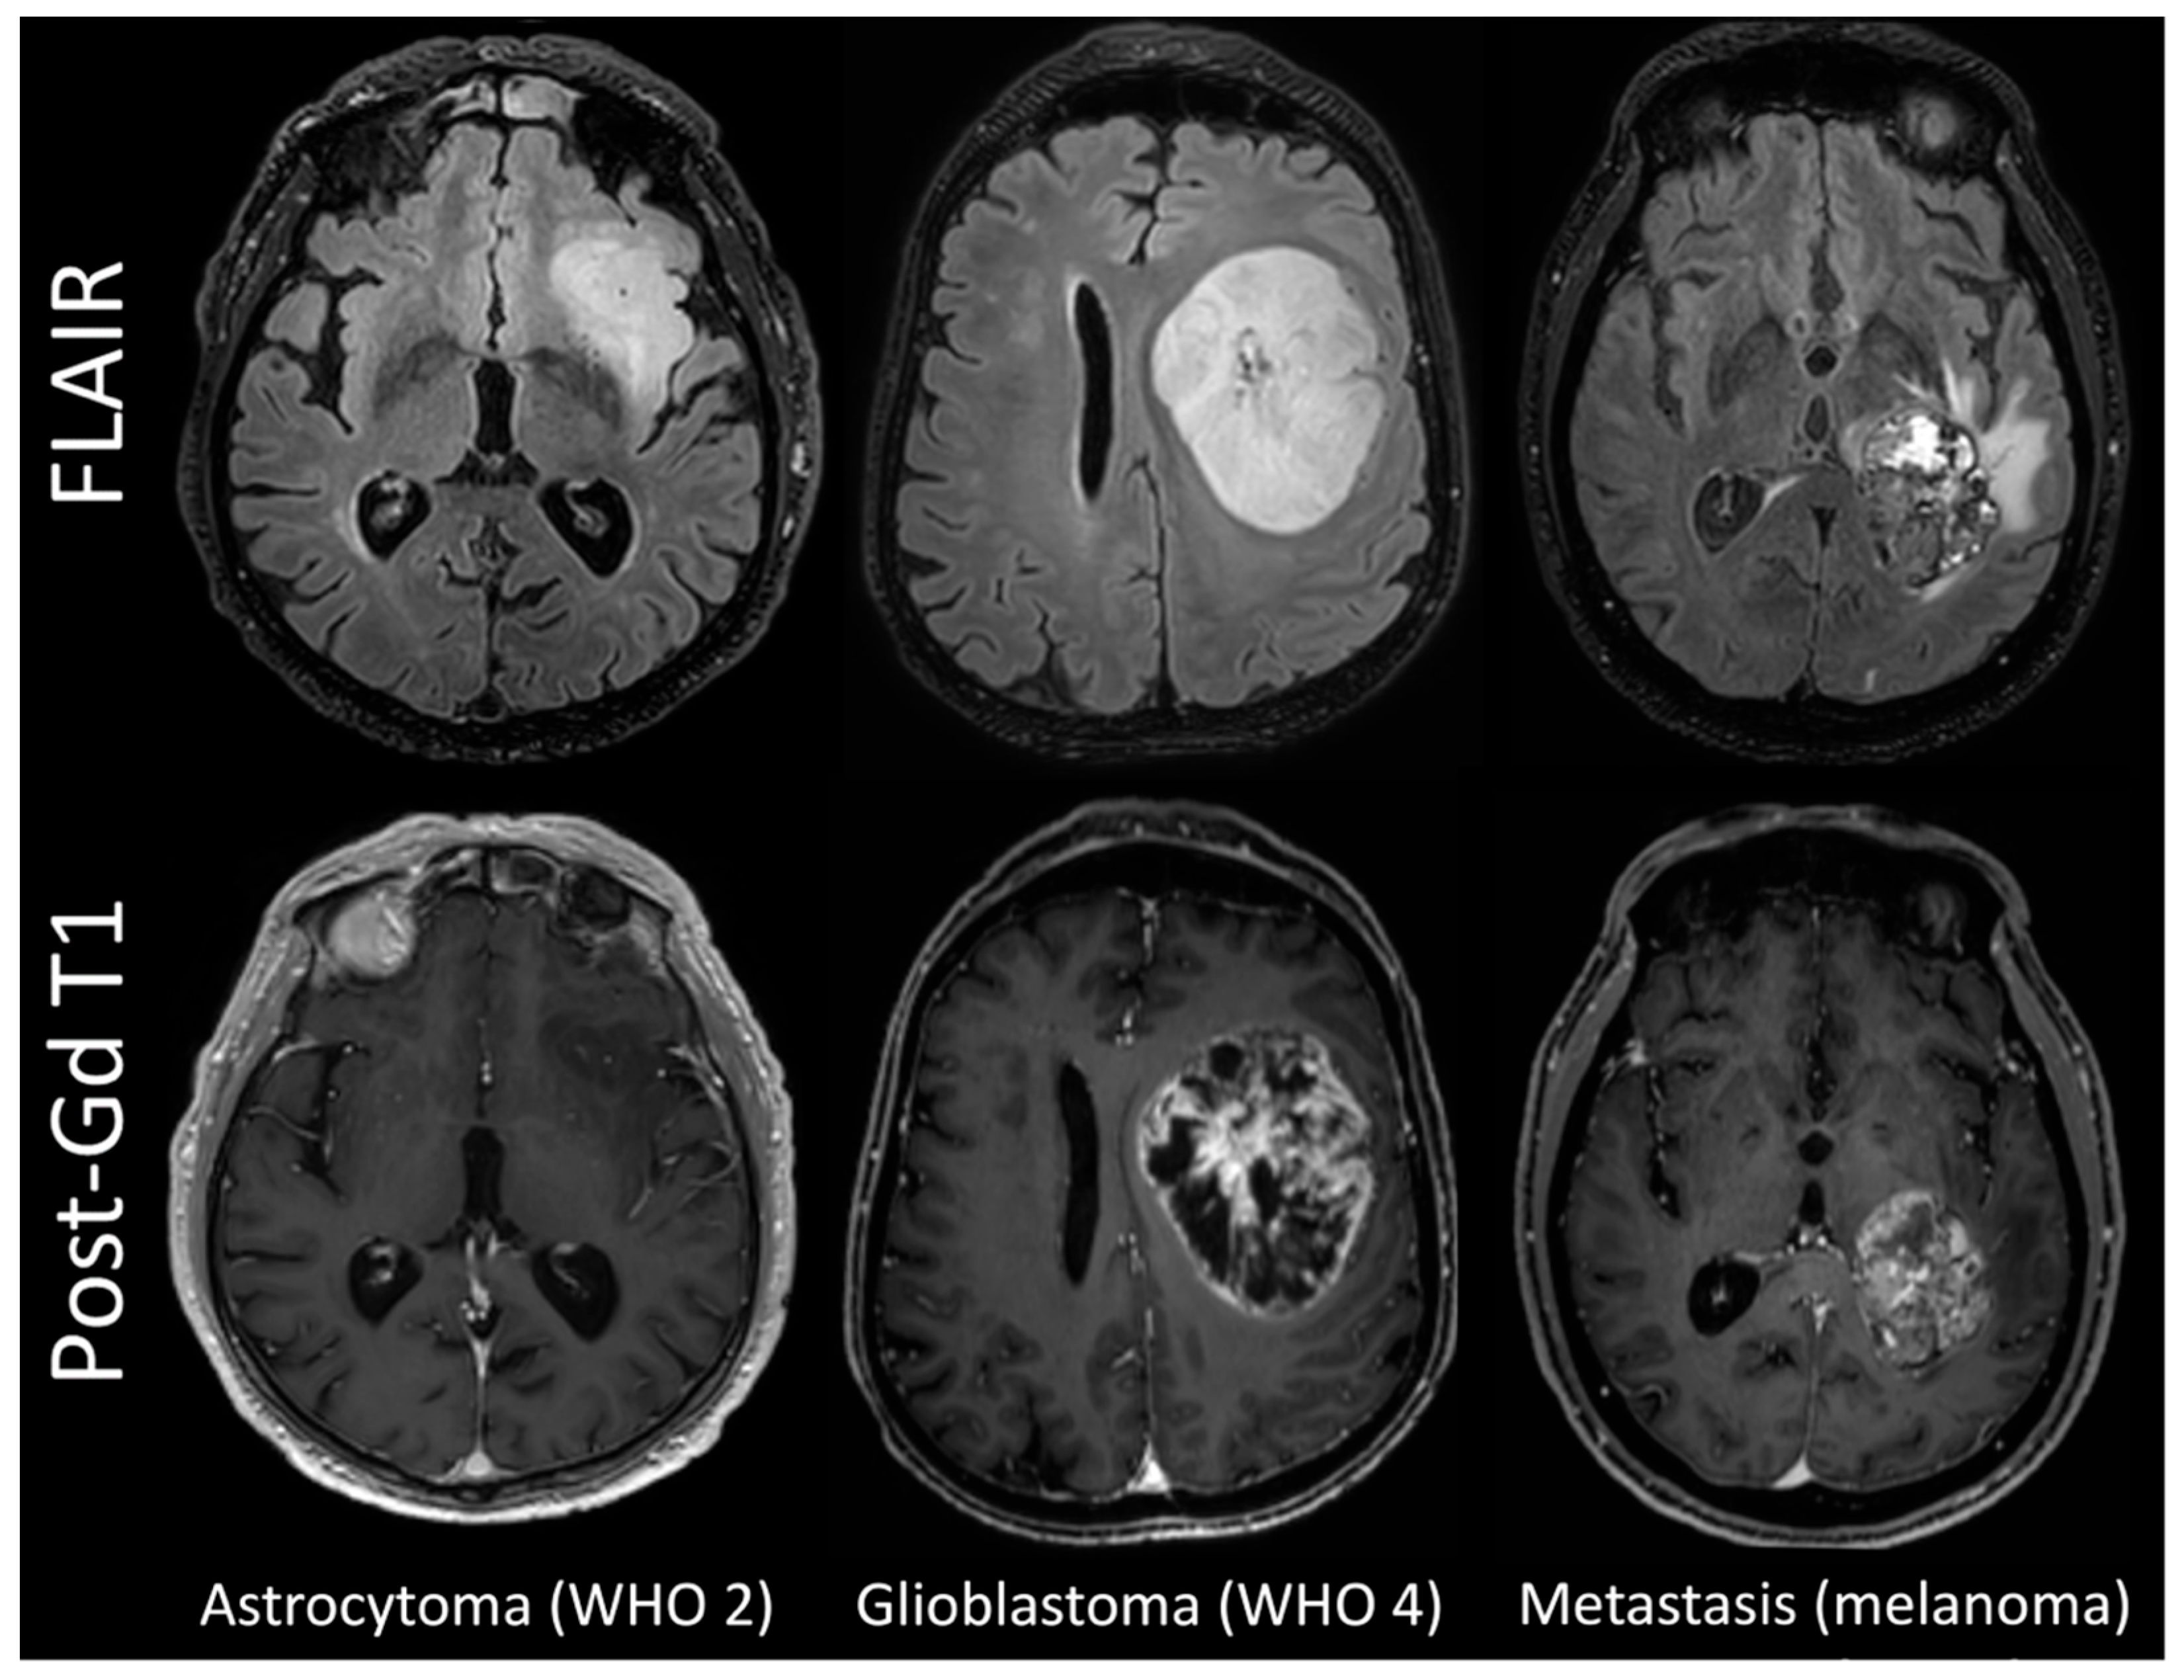

3.1. Patient Population

3.3. Comparison between Histotypes